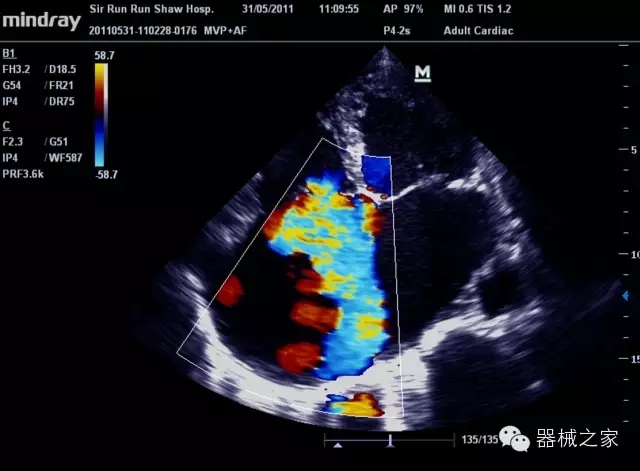

經(jīng)典產(chǎn)品:M7(星鉆)

臨床圖片賞析

產(chǎn)品特點(diǎn)

·裝載有采用Multi-Core多核處理的非嵌入式平臺,成像效率大大提高,并且能夠給用戶帶來高速、多任務(wù)并行信號處理體驗(yàn);

·優(yōu)秀的圖像效果、強(qiáng)大的功能體驗(yàn)、豐富的探頭選擇、合理的便攜式設(shè)計(jì),全中文顯示及病人管理界面,使得M7在任何場合、任何時候都能快速響應(yīng)更好的心血管、腹部、婦產(chǎn)、小器官等常規(guī)超聲檢查以及肌骨、神經(jīng)、顱腦、術(shù)中等新興領(lǐng)域的使用需求;

8倍波束并行處理系統(tǒng)

·在便攜式緊湊平臺上采用更多倍波束并行接收信號處理模式,無論二維還是彩色血流圖像狀態(tài)下,擁有更靈敏的回波頻移捕獲能力,大大提高時間分辨率,尤其使得心血管表現(xiàn)更為突出;

PSHI?寬帶頻移諧波技術(shù)

·在普通組織諧波的基礎(chǔ)上,通過精確控制的波束形成器,發(fā)射兩組具有相位偏差反向的信號,并采用并行信號處理,數(shù)字化合成并采樣回波信號,在高靈敏度的濾波器的處理過程中獲取更純凈的諧波信號,使圖像具有更加出眾的細(xì)節(jié)分辨率;

iClear®+iBeam?

·智能化按線復(fù)合多角度獲取聲束的原始信號,配合智能化的斑點(diǎn)噪聲識別及控制處理技術(shù),整體提高組織結(jié)構(gòu)細(xì)節(jié)分辨率,任何時候都能快速響應(yīng),更好的滿足心血管的使用需求;

支持全新3T工藝探頭群

·包括探頭材料、結(jié)構(gòu)設(shè)計(jì)、加工工藝三方面的革新技術(shù)給圖像帶來品質(zhì)的飛躍;

CFDA注冊證編號

·粵食藥監(jiān)械(準(zhǔn))字20132230475